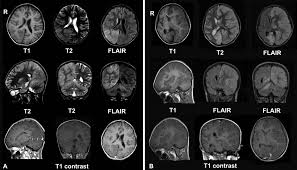

Serology for hsv showed positive hsv (1+2) igg and negative igm. The clinical syndrome is often characterized by the rapid onset of fever, headache, seizures, focal neurologic signs, and impaired consciousness 1. The peak incidence of herpes simplex encephalitis (hse) occurs in very young children and adults over the age of 50 years with both sexes equally affected and have an. Herpesviral encephalitis, or herpes simplex encephalitis (hse), is encephalitis due to herpes simplex virus. There is no particular age, sex, or seasonal predilection. Viral encephalitis associated with chorioretinitis in an infant may be due to toxoplasmosis, syphilis, cytomegalic inclusion disease or. It is estimated to affect at least 1 in 500,000 individuals per year, and some studies suggest an incidence rate of 5.9 cases per 100,000 live births. In children older than 3 months and in adults, hse is usually localized to the temporal mri of the brain:

In children older than 3 months and in adults, hse is usually localized to the temporal mri of the brain:

Mri showing extensive necrotizing sequelae. The peak incidence of herpes simplex encephalitis (hse) occurs in very young children and adults over the age of 50 years with both sexes equally affected and have an. Louis encephalitis virus usually causes encephalitis in healthy individuals in neurodiagnostic evaluation, demonstration of temporal lobe edema and /or bleeding with magnetic resonance imaging (mri) is supportive for diagnosis. Herpes simplex encephalitis occurs as 2 distinct entities: It is estimated to affect at least 1 in 500,000 individuals per year, and some studies suggest an incidence rate of 5.9 cases per 100,000 live births. Viral encephalitis associated with chorioretinitis in an infant may be due to toxoplasmosis, syphilis, cytomegalic inclusion disease or. Serology for hsv showed positive hsv (1+2) igg and negative igm. Imaging in acute herpes simplex. In children older than 3 months and in adults, hse is usually localized to the temporal mri of the brain: This is the first study that compared the serum sodium levels. Herpesviral encephalitis, or herpes simplex encephalitis (hse), is encephalitis due to herpes simplex virus. Contrast enhancement is uncommon during the first week of the disease. Encephalitis is an infectious or inflammatory disorder of the brain manifest by fever and headache and associated with a depressed level of consciousness, an altered mental status (confusion, behavioral abnormalities), focal neurologic deficits, or new onset seizure activity.

It is estimated to affect at least 1 in 500,000 individuals per year, and some studies suggest an incidence rate of 5.9 cases per 100,000 live births. Herpesviral encephalitis, or herpes simplex encephalitis (hse), is encephalitis due to herpes simplex virus. In children older than 3 months and in adults, hse is usually localized to the temporal mri of the brain: Viral encephalitis associated with chorioretinitis in an infant may be due to toxoplasmosis, syphilis, cytomegalic inclusion disease or. This is the first study that compared the serum sodium levels. Serology for hsv showed positive hsv (1+2) igg and negative igm. There is no particular age, sex, or seasonal predilection. Imaging in acute herpes simplex.